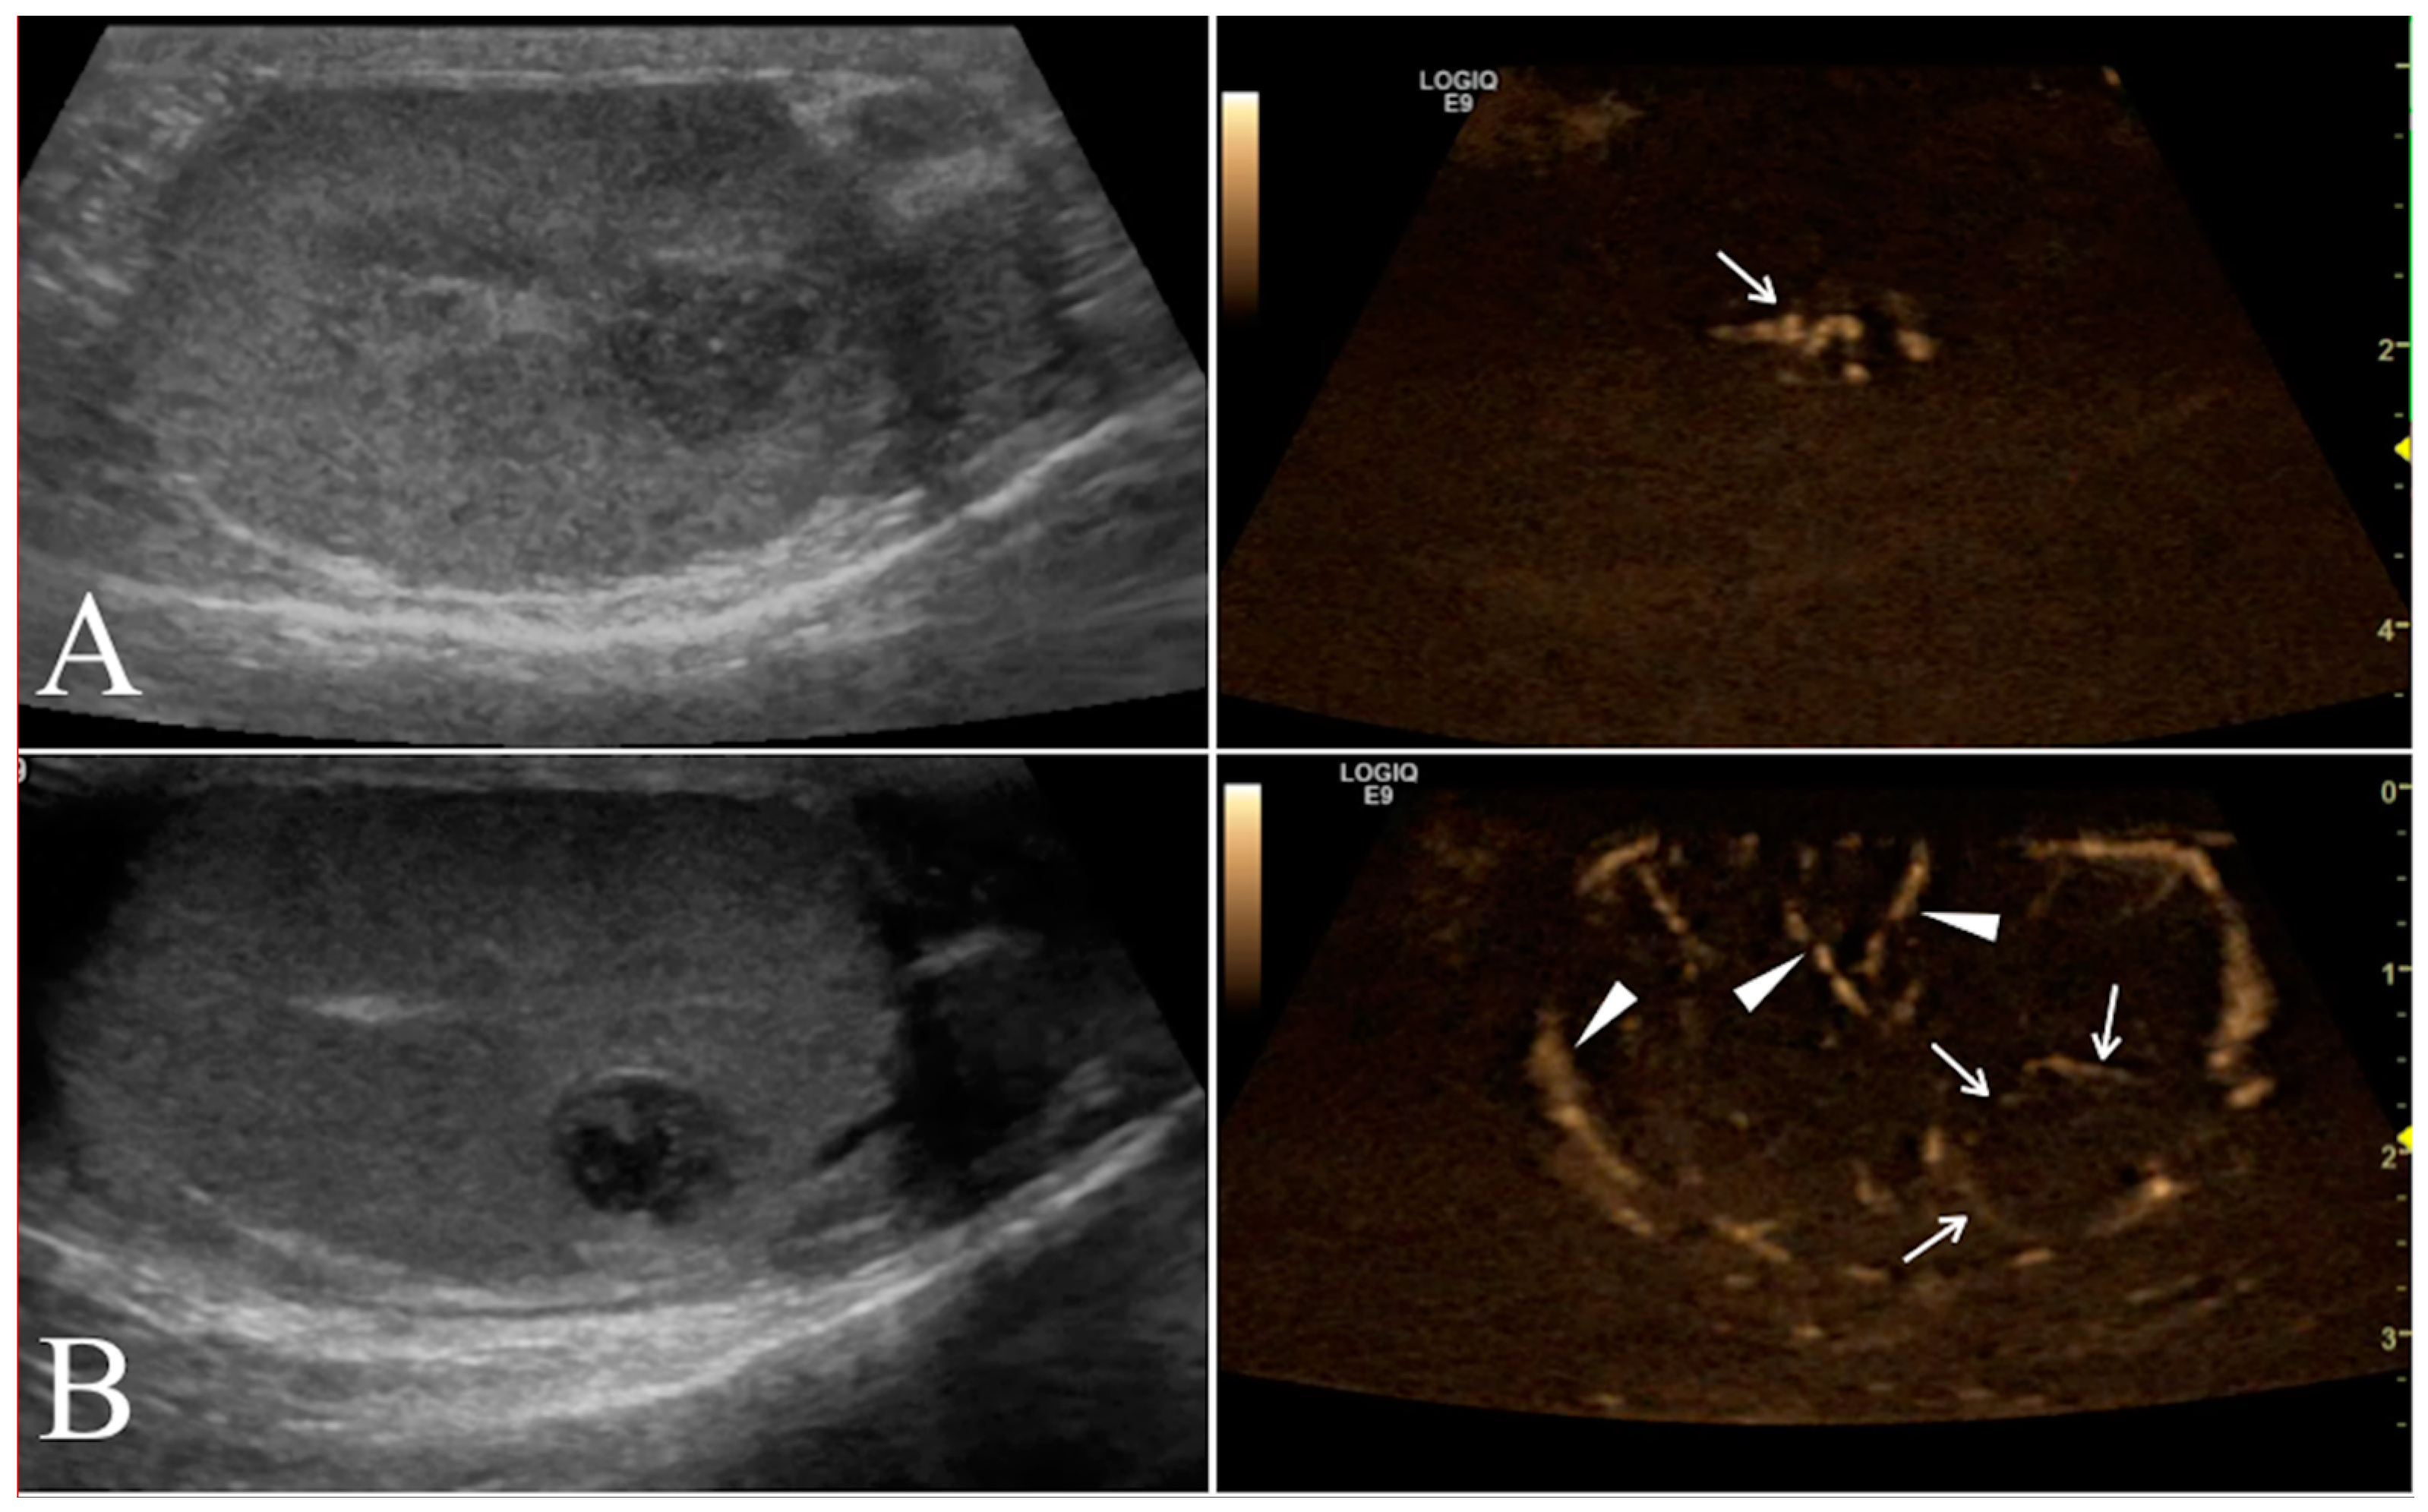

Contrast enhancement patterns during the distribution phases were first evaluated qualitatively for each testicle to assess the following parameters compared to normal testicular parenchyma: (i) arrival time of contrast medium into the lesion (early or late); (ii) wash-in enhancement (homogeneous or inhomogeneous; (iii) intensity of contrast (hyperenhanced, isoenhanced, or hypoenhanced) (Figure 4).

Figure 4. Left testicle leydigoma of a 11 year old Italian Mastiff (the same of Figure 2). The left panel shows the sagittal B-mode ultrasound highlighting a focal hyperechoic nodule with homogeneous echotexture and regular margin. Representative contrast-enhanced ultrasound images of different contrast distribution phases are represented in the right panels. After 16 s from contrast injection it is possible to appreciate an early distribution of the contrast within the lesions (Arrows) compared to the surrounding parenchyma (A). Later (25 s) the contrast medium distributes homogeneously within the lesion that remain hyperenhanced compared to the normal testicle (B).